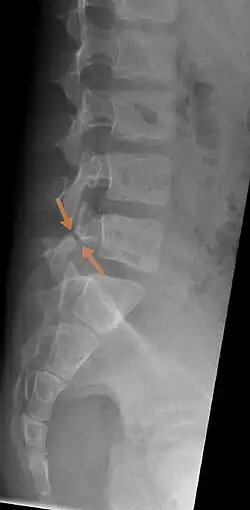

| Arrows show break in pars interarticularis at L5. X-Ray of lumbar spine, lateral projection, in an 11-year-old boy | |

X-Ray

X-rays (electromagnetic radiation) are projected through the body to produce an image of its internal structures. The radiation is more attenuated (absorbed) by the denser tissues of the body (i.e. bone) than the softer tissues (i.e. muscles, organs, etc.) creating a picture composed of shades of grey ranging from white to black. A vertebra with a fracture or defect of the pars interarticularis will have a dark mark through this region of bone. Since this is difficult to see on the AP (anterior posterior) x-ray view an oblique x-ray of the lumbar spine can usually identify the spondylolysis. If inconclusive a further CT scan can produce a 3-dimensional images to more clearly show the defect although the exam increases the patients radiation dose by at least an order of magnitude than plain x-rays.[16][17]